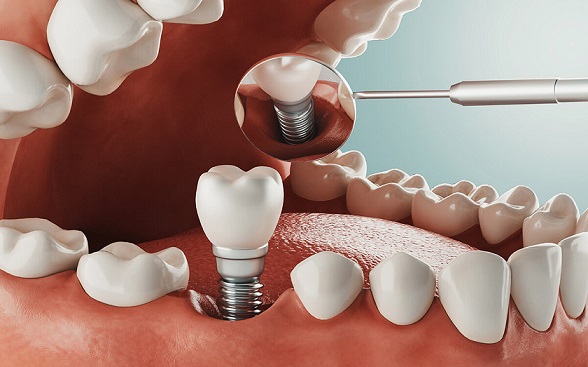

بله، در برخی موارد، پس از انجام عمل ایمپلنت دندان، ممکن است ورم در محلی که عمل ایمپلنت انجام شده است، رخ دهد. این ورم ممکن است ناشی از واکنش های التهابی باشد که به جراحی و وارد کردن ایمپلنت در بافت های فک و دهان بر می گردد. این واکنش ها به عنوان پاسخ بدن به جسم خارجی در محل ایمپلنت ایجاد می شوند. همچنین ورم معمولا در محدوده انجام عمل ایمپلنت ایجاد می شود و ممکن است همراه با علائمی مانند درد، قرمزی، حساسیت و تورم به همراه باشد. این وضعیت ممکن است برای مدت کوتاهی پس از عمل ادامه داشته باشد و به مرور زمان بهبود یابد. که باید مراقبت های ایمپلنت دندان مانند حرف زدن بعد از جراحی ایمپلنت و آب نمک بعد از ایمپلنت برای جلوگیری از عفونت جدی گرفته شود. اگر هم دچار درد شدید راه های درمان سریع دندان درد در شب می تواند به شما کمک کند.

درمان ورم صورت بعد از ایمپلنت دندان معمولا به واکنشی که بدن به جراحی و ایمپلنت نشان میدهد، مرتبط است. مراقبت های بعد از ایمپلنت دندان موجب کمتر شدن ورم بعد از ایمپلنت می شود. اگر ورم ناشی از واکنشات طبیعی و التهابی پس از عمل ایمپلنت باشد، تدابیر زیر می توانند به کنترل و کاهش آن کمک کنند:

- استراحت: بعد از انجام جراحی بهتر است به بدن زمان بیشتری برای استراحت دهید تا سریعتر محل زخم ترمیم شود. اجتناب از فعالیت های جسمانی شدید و استراحت بهترین راه برای کاهش ورم است.

- استفاده از یخ: استفاده از یخ در محل تورم برای مدت زمان کوتاه می تواند تورم را کاهش دهد. این کار را با مداومت انجام دهید، اما از مستقیم قرار دادن یخ بر روی پوست خودداری کنید. بهتر است از یک پارچه یا دستمال نازک برای ایجاد فاصله با پوست استفاده کنید.

- مصرف داروهای ضدالتهابی: در صورت تجویز داروهای ضد التهاب توسط دندانپزشک، مصرف آن ها می تواند به کاهش التهاب و ورم کمک کند. با این حال، به موقع و طبق دستور پزشک داروها را مصرف کنید.

- مصرف مایعات: مصرف مقدار زیادی آب و مایعات می تواند به کاهش ورم کمک کند و از تجمع سایش در محل ورم جلوگیری کند.

- تغذیه سالم: تغذیه به خوبی می تواند به تقویت سیستم ایمنی بدن و کاهش ورم کمک کند. مصرف مواد غذایی غنی از آنتی اکسیدان ها مانند میوه ها، سبزیجات و مصرف ویتامین C مفید است.

- مراقبت دهانی: به دقت دستورات پس از جراحی ایمپلنت را دنبال کنید و از دندان های اطراف ایمپلنت به صورت ملایم مراقبت کنید تا به التهابات بیشتری منجر نشود از مصرف سردی ها و داغی ها بپرهیزید تا از احتمال تحریک تورم و دلایل منجر به قورت دادن پیچ ایمپلنت جلوگیری کنید.